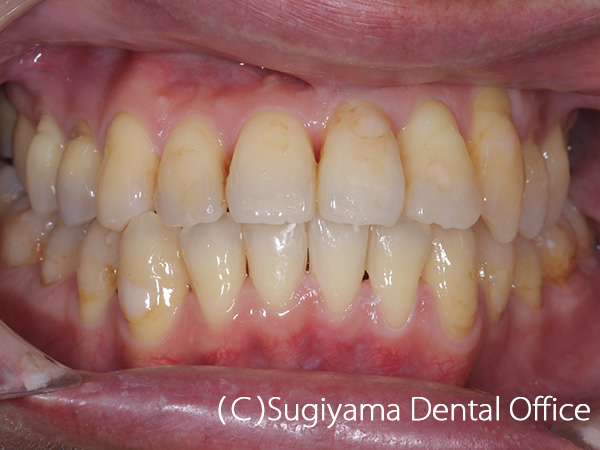

術前症例写真

術後症例写真

10歳の女性です。 術前写真を見ると、上の前歯2本が内側に傾斜していることがわかります(丸印)。 このような歯の傾斜によって下のあごの位置が奥に押し込まれ顎関節症になる方が少なくありません。

術後1年後には綺麗な歯並びになっただけでなく、機能的なあごの運動ができるようになりました。